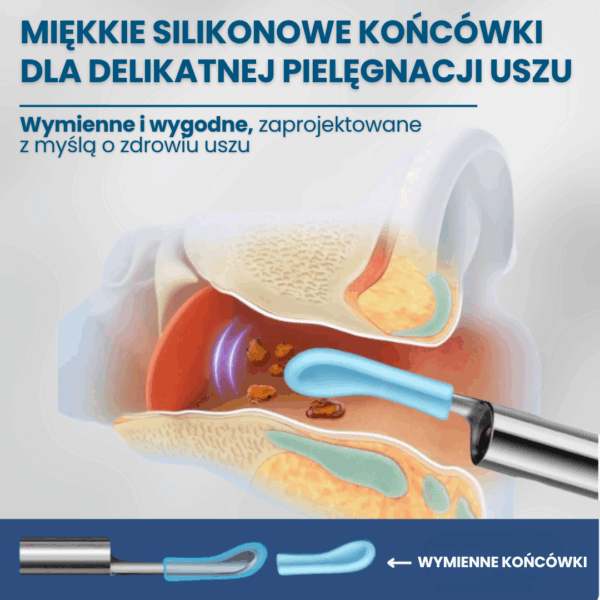

Koniec z ryzykiem urazów i infekcji — patyczki często powodują podrażnienia, infekcje i perforację błony bębenkowej. Pełna kontrola dzięki obrazowi HD 1080p — widzisz woskowinę i swobodnie ją usuwasz, zamiast ją wpychać.

Higieniczne i oszczędne — wielorazowe końcówki redukują odpady i koszty wymiennych patyczków. Szybka ulga — natychmiastowy efekt komfortu i czystości uszu bez wizyt u specjalisty.

Szybka ulga — natychmiastowy efekt komfortu i czystości uszu bez wizyt u specjalisty.